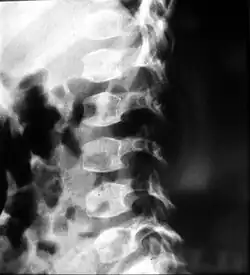

X-ray of the spine in a patient with spondyloepimetaphyseal dysplasia

People with spondyloepiphyseal dysplasia are short-statured from birth, with a very short trunk and neck and shortened limbs. Their hands and feet, however, are usually average-sized. This type of dwarfism is characterized by a normal spinal column length relative to the femur bone. Adult height ranges from 0.9 meters (35 inches) to just over 1.4 meters (55 inches). Curvature of the spine (such as kyphoscoliosis and lordosis) progresses during childhood and can cause problems with breathing. Changes in the spinal bones (vertebrae) in the neck may also increase the risk of spinal cord damage. Other skeletal signs include flattened vertebrae (platyspondyly), a hip joint deformity in which the upper leg bones turn inward (coxa vara), and an inward- and downward-turning foot (called clubfoot). Decreased joint mobility and arthritis often develop early in life. Medical texts often state a mild and variable change to facial features, including cheekbones close to the nose appearing flattened, although this appears to be unfounded. Some infants are born with a cleft palate. Severe nearsightedness (high myopia) is sometimes present, as are other eye problems that can affect vision such as detached retinas. About one-quarter of people with this condition have mild to moderate hearing loss.[2]